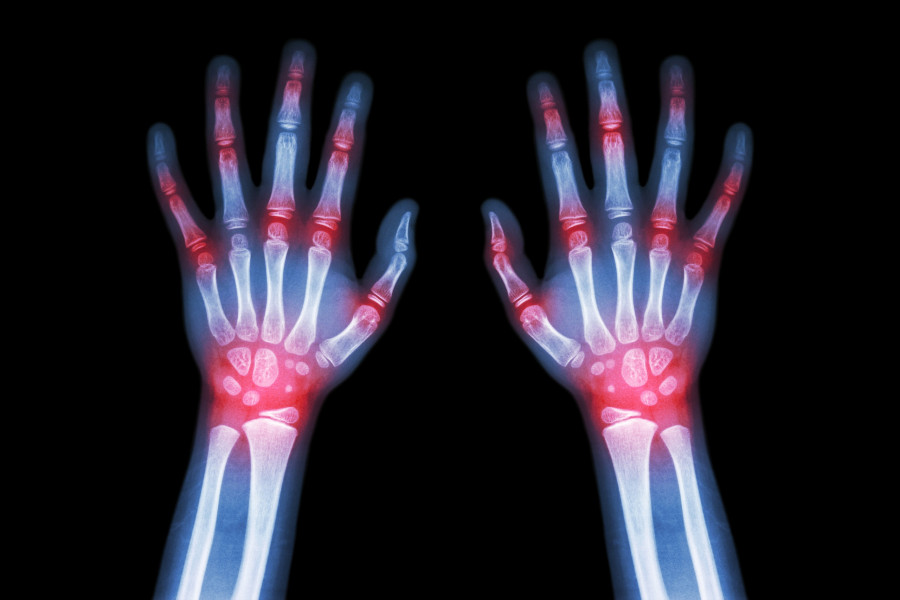

Η αρθρίτιδα στα δάχτυλα μπορεί να ξεκινήσει ανεπαίσθητα, αλλά εάν δεν αντιμετωπιστεί μπορεί να εξελιχθεί σε δυσκαμψία, πόνο και μειωμένη λειτουργία του χεριού.

Η έγκαιρη αναγνώριση είναι ζωτικής σημασίας, επειδή η άμεση θεραπεία μπορεί να επιβραδύνει τη βλάβη στις αρθρώσεις, να διατηρήσει την κινητικότητα και να βελτιώσει την ποιότητα ζωής.

Ο ορθοπεδικός θα ελέγξει την ευαισθησία των αρθρώσεων, το εύρος κίνησης και τις παραμορφώσεις. Οι ακτινογραφίες μπορεί να αποκαλύψουν απώλεια χόνδρου ή αλλαγές στα οστά, ενώ οι εξετάσεις αίματος μπορούν να ανιχνεύσουν αυτοάνοσους δείκτες ρευματοειδούς ή ψωριασικής αρθρίτιδας. Η έγκαιρη αξιολόγηση είναι απαραίτητη για την προσαρμογή της θεραπείας και την πρόληψη μη αναστρέψιμης βλάβης των αρθρώσεων.